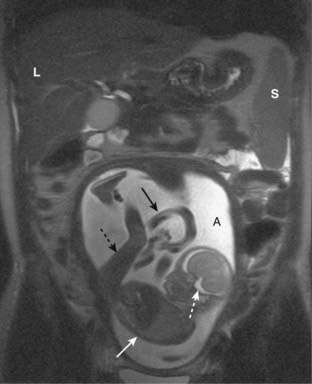

Figure 20-13 MRI in pregnancy.

Coronal T2-weighted image demonstrates an intrauterine pregnancy. The maternal liver (L) and spleen (S) are partially imaged. The bright amniotic fluid (A) and fetal CSF (dotted white arrow) help us to recognize this image as a T2-weighted image. The fetal body (solid white arrow) and leg (dotted black arrow) can be seen clearly. The umbilical cord (solid black arrow) is partially visualized.